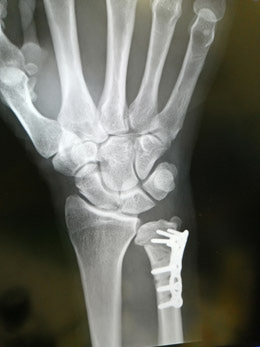

2週間ぶりの尺骨レントゲンです。

太い橈骨より尺骨が骨切短くなって

プレートボルト固定になってます。

尺骨突き上げ症候群は、短縮骨切り術で短くなり

TFCC箇所が広くなり、

これで突き上げ圧での痛み再損傷リスクもなくなるようです。

術後

術後、尺骨短くなっているの分かるかと思います。